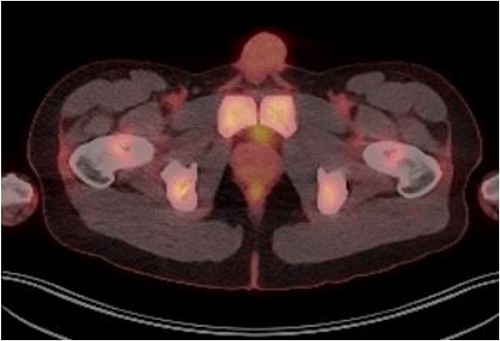

Laboratory tests of full blood count and liver function test were unremarkable with prostate specific antigen of 0.53. Mid-stream urine MCS did not show any infection and urine cytology was negative. Renal function test revealed progressive worsening of previously normal eGFR down to 27 ml/min. Initial renal tract ultrasound (Fig. 1) showed enlarged prostate indenting into the bladder base with high post micturition urine residual volume of 185 ml but no hydronephrosis. CT KUB (Fig. 2) showed irregularly enlarged prostate with bilateral hydroureteronephrosis. MRI prostate showed enlarged prostate with PIRADS 5 amorphous mass suspicious for carcinoma involving bilateral seminal vesicles and right vesicouretric bladder. FDG PET (Fig. 3) showed unusual distribution pattern of lymphoma involving the prostate with bilateral symmetrical renal, early pulmonary, and possibly right thyroid lobe involvement.

PET FDG scan pre-R-CHOP chemotherapy showing disease activity in the prostate.